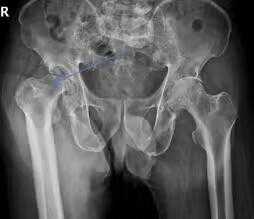

一70岁患者男性右下肢缩短,右髋活动受限。专科检查发现其腹部柔软,略压痛,无反跳痛,Murphy征阴性,移动性浊音阴性。双下肢无肿胀,右下肢较对侧缩短约3cm,右侧大转子上移,腹股沟处压痛明显。双髋关节无肿胀,双髋屈伸活动明显受限,伸直:20度受限,屈曲100度,患肢末梢血运好,皮肤感觉好,双手不自主颤抖。辅助检查发现,其骨盆正位数字化摄影(DR)双侧股骨头坏死,两侧髋关节病q变,发育异常。

术前经过专家会诊,给出详细手术方案,完善血常规,凝血常规,感染四项等检查。在患者及家人同意后实施全髋关节置换术。术后给予预防感染,消肿,止痛等治疗,并指导患者行功能锻炼。